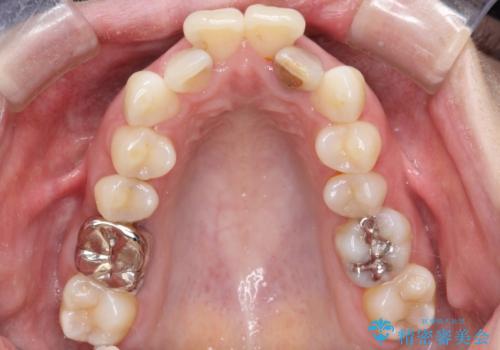

- 全体的ながたがたを主訴に来院されました。

上顎の前歯は前方に傾斜して、下顎の前歯は強いガタガタが見られました。

前から4番目の歯を上下左右合計2本抜歯して、歯並びを整える計画としました。

ワイヤー矯正にて治療しました。